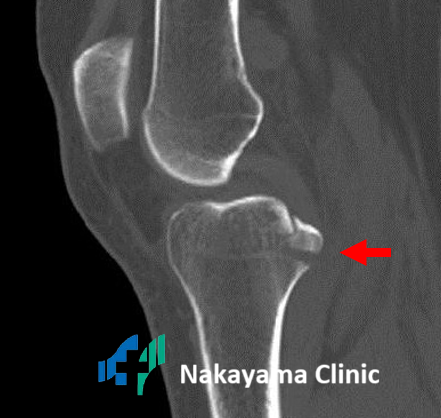

膝内側の骨髄浮腫 |

内側半月板後根損傷 |

特に、半月板の後ろ側(後根)が断裂すると、「ブチッ」という音とともに激痛が走り、急激に膝の状態が悪化することがあります。

これを見逃すと、骨が壊死(えし)してしまい、歩行が困難になるほどの痛みに発展する可能性も。

とても怖い損傷です。

大きな骨折はすぐにわかりますが、小さな骨折、特に後十字靭帯が付着している部分が剥がれる「裂離骨折(れつりこっせつ)」は、レントゲンでも見落とされることがあるのです。

膝を曲げたまま転倒した際に起こりやすく、歩いてクリニックに来られる方も少なくありません。

膝内側の骨髄浮腫

内側半月板後根損傷